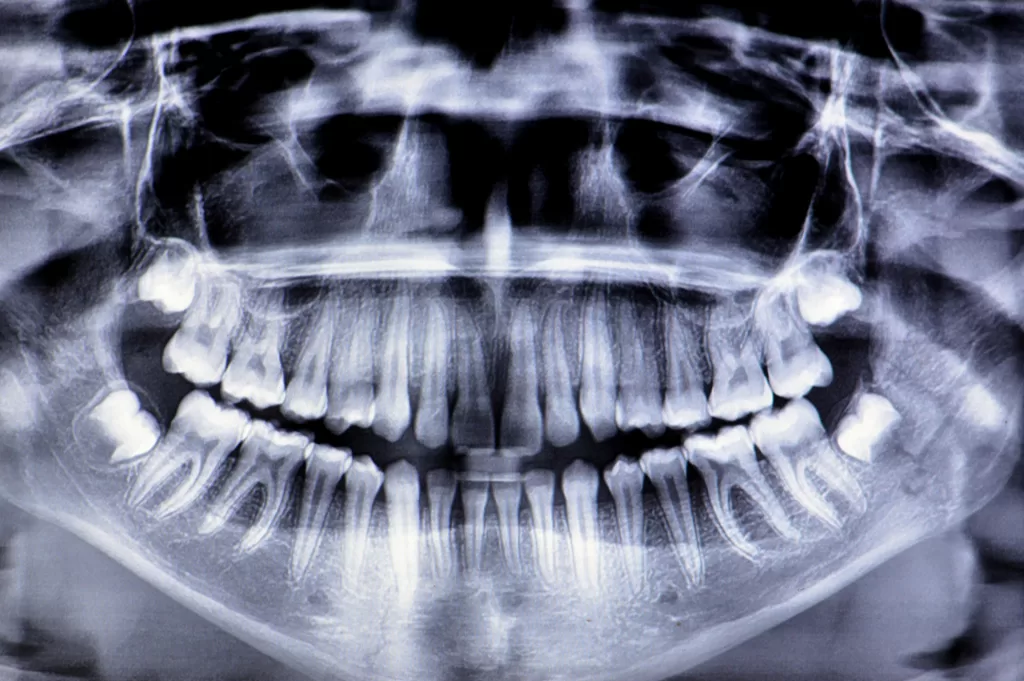

- Radiografia panorâmica de mandíbula/maxila (ortopantomografia): É uma radiografia que mostra uma visão geral de toda a sua boca em uma única imagem: todos os dentes (inclusive os que ainda não nasceram, como o siso), a mandíbula, a maxila, as articulações da mandíbula (ATM) e os seios da face. É excelente para um primeiro diagnóstico, para planejar tratamentos ortodônticos ou extrações de siso. Pode ser feita com ou sem traçado cefalométrico (medidas para ortodontia).